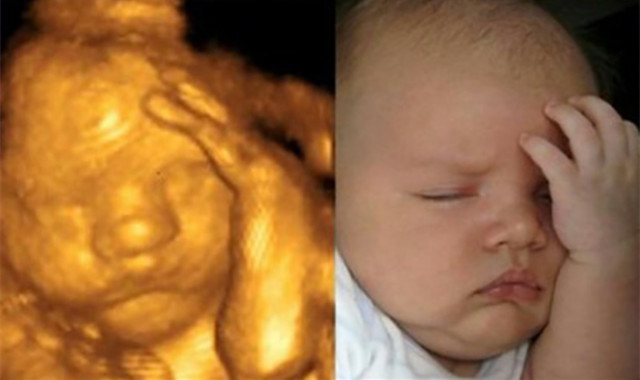

之前看过一组宝妈晒的照片,小婴儿刚出生时确实跟四维照片很像,包括一些动作跟在肚子里是一样的。

像这个小宝宝出生后睡觉,手依然喜欢放在检查时那个位置,表情也跟四维照片很像。

不过出生后宝宝的颜值已经有很大提升了,因为产检时胎宝宝每天还在成长中,而且泡在羊水里有些“肿眼泡”,所以颜值有些低准爸妈们不必太过担心。